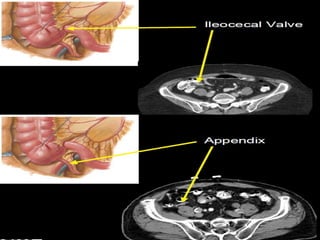

Small Intestine  Thebody’s major digestive organ  Site of nutrient absorption into the blood  Muscular tube extending from the pyloric sphincter to the ileocecal valve  Suspended from the posterior abdominal wall by the mesentery

• 49.

Subdivisions of theSmall Intestine  Duodenum(25cm) Attached to the stomach Curves around the head of the pancreas Fixed retroperitoneal structure  Jejunum (2.5m) Attaches anteriorly to the duodenum  Ileum (3.5m) Extends from jejunum to large intestine

• 50.

• 56.

Cecum – pocketat proximal end with Appendix Colon Ascending colon - on right, between cecum and right colic flexure Transverse colon - horizontal portion Descending colon - left side, between left colic flexure and Sigmoid colon - S bend near the terminal end Regions of Large Intestine Rectum –terminal end is anal canal - ending at the anus - which has internal involuntary sphincter and external voluntary sphincter